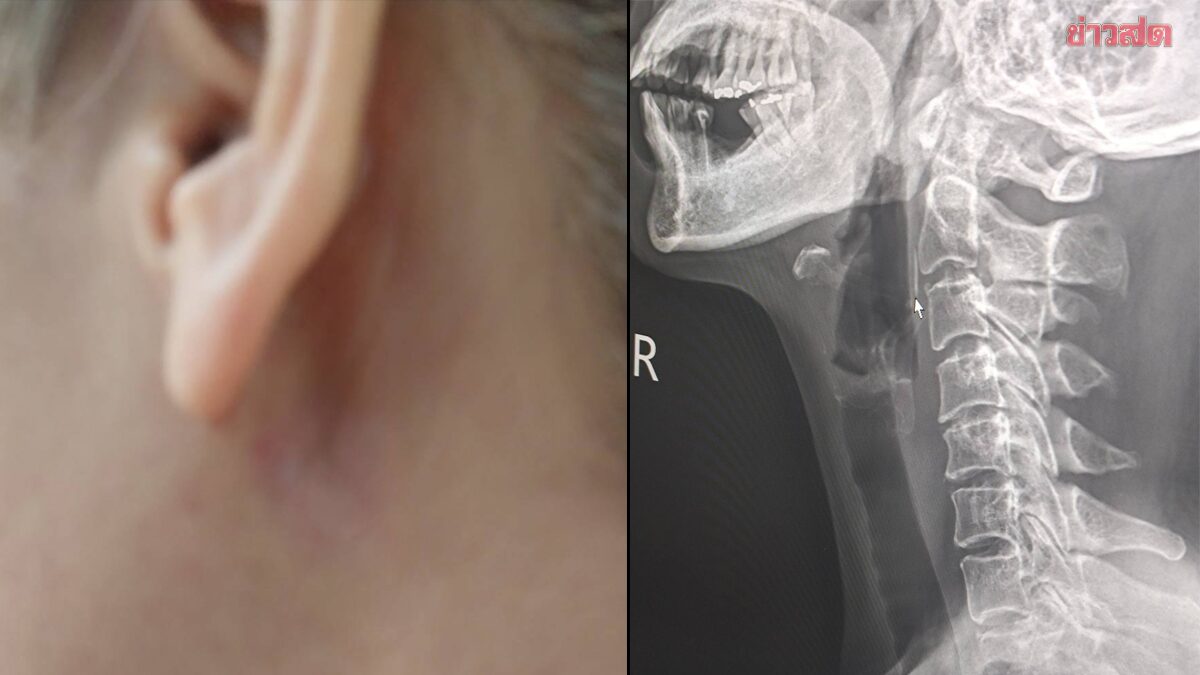

หญิงแชร์เรื่องขนลุก ‘ก้างปลาติดคอ’ 11 วัน คิดว่าเป็นไร ไหลลงไปแล้ว เพราะไม่มีอาการเจ็บคอเวลาทานอาหาร แต่อยู่ดีดีก้างปลาโผล่ทิ่มทะลุออกมาข้างคอ 26 เม.ย. 69 – สังคมออนไลน์แชร์โพสต์ของผู้ใช้เฟซบุ๊ก Rungravee Chaiwirattikul ที่ออกมาเขียนถึงอุทาหรณ์จาก “ก้างปลา” ที่ติดคอ โดยระบุใจความดังนี้ ผู้โพสต์ก้างปลาติดคอ ตั้งแต่วันที่ 14 เม.ย. ที่ผ่านมา ไปหาหมอมา 3 คน หมอบอกไปในทิศทางเดียวกันว่าไม่น่าจะติดอยู่แล้ว ซึ่งตัวผู้โพสต์เองก็คิดเช่นกัน เหตุผลสำคัญคือ เพราะในคอไม่มีอาการเจ็บคอเวลาทานอาหาร แต่ถึงกระนั้นเธอยังสงสัยว่าทำไมปวดตรงข้างคอด้านนอกหลังใบหูอยู่ จึงพยายามเอามือจับกดดูทุกวัน พร้อมตั้งข้อสงสัยว่าก้างปลามันสามารถทิ่มออกมาด้านนอกได้ไหม ผ่านมาถึงวันที่ 24 เม.ย. ตอนตี 2 ผู้โพสต์ที่เกิดความสงสัย จึดตัดสินใจกดลงไปอีกครั้งบริเวณข้างคอหลังใบหู เธอเริ่มมั่นใจแล้วว่าต้องเป็นก้างปลาแน่ ๆ แต่ก็ไม่กล้าดึง เพราะกลัวโดนเส้นเลือดหรือเส้นประสาท แต่ในวันที่ 25 เม.ย. ตอนเช้า ความประหลาดที่ไม่น่าเชื่อคือ ก้างปลาโผล่ออกมาสะดุดมือตอนล้างหน้าที่หลังหู เมื่อเอามือจับดู ก้างปลาที่แหลมเหมือนปลายเข็มโผล่ออกมานอกผิวหนัง เธอจับค่อย ๆ […]